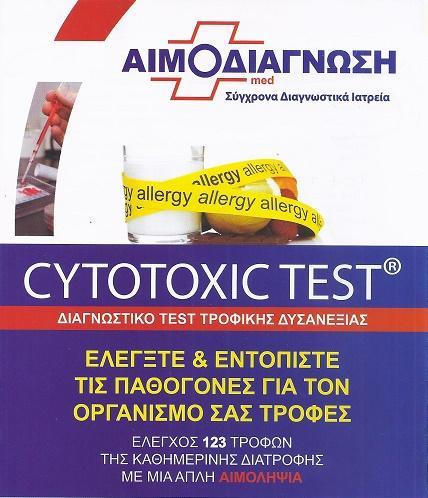

Μικροβιολογικό εργαστήριο Καπανδρίτι, τεστ παπ μαστού, τεστ τροφικής δυσανεξίας Καπανδρίτι